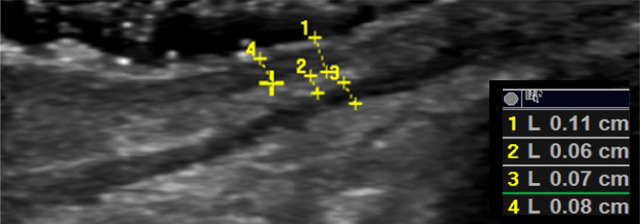

Methods: This is a prospective case-control study. Patients were recruited from the Oculoplastic Service of the Department of Ophthalmology at the University Hospital of Heraklion, Crete, Greece. The diagnosis of floppy eyelid syndrome was based on the eversion of the upper eyelid upon unassisted digital traction. Cataract surgery candidates without floppy eyelid syndrome were consecutively recruited as controls. Patients with a history of previous eyelid pathology or surgery were excluded. Ultrasound examination was performed using high-frequency linear probes (GE E9) for B-mode imaging and shear wave and strain elastography. Upper airway measurements included tongue thickness and upper airway length. Clinical and demographic findings were recorded.

Results: Twenty-eight patients were included (14 with floppy eyelid syndrome, 14 controls). Orbicularis muscle elasticity in kPa was significantly higher in the floppy eyelid syndrome group, compared with controls (independent samples t-test score 2.64, p = 0.04). Tongue thickness and upper airway length were also significantly correlated with several eyelid B-mode and elastography parameters in patients with floppy eyelid syndrome, including subcutaneous fat and orbicularis muscle thickness and elasticity.